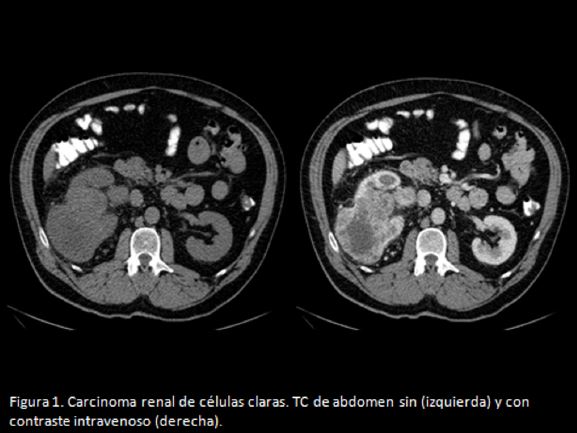

El carcinoma de células renales (CCR) es el tumor maligno renal más frecuente (90%). Presenta diferentes subtipos histológicos, el más frecuente de ellos es el carcinoma de células claras (70%).